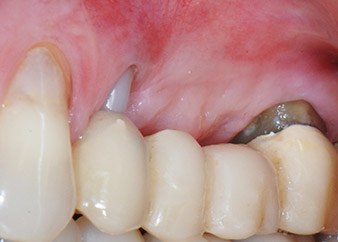

One month later, on the day of surgery, pain and inflammation at tooth 24 were minimal, but mobility of Miller class 2 was still present. After opening the flaps and cleaning the periapical and peri radicular infected tissue, the extent of the bone defect became obvious (Figs. 2 and 3).

At the buccal root, all vestibular and distal bone was missing. Attachment was essentially restricted to the palatal root, underlining the preliminary poor prognosis. Tooth 27 also showed a reduced horizontal attachment and a minimal apical rarefaction (cf. Fig. 1) without clinical symptoms.

total loss of bone and attachment

Fig. 2 and 3: After raising flaps, one month after endodontic revision and initiation of full-mouth periodontal therapy, the buccal root of tooth 24 showed a total loss of bone and attachment.